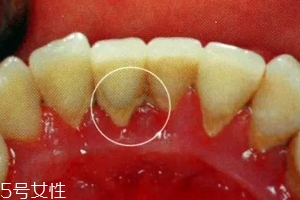

牙結(jié)石是不會(huì)自動(dòng)脫落的,因?yàn)樗卫蔚母街谘例X表面,當(dāng)然有時(shí)候會(huì)有極少數(shù)的牙結(jié)石會(huì)因?yàn)槟闼⒀阑蛘哂醚篮瀯兟?,只是極少數(shù)現(xiàn)象。所以有了牙結(jié)石千萬(wàn)不能忽視,它不會(huì)像感冒一樣會(huì)自行康復(fù)的,它們只會(huì)在你的牙齒表面沉積下來(lái),日積月累,使你的口腔患上炎癥,這樣只會(huì)導(dǎo)致牙齦炎癥逐漸加重,并發(fā)展為牙周炎,最終導(dǎo)致牙齒松動(dòng)脫落。不要奢求牙結(jié)石會(huì)自動(dòng)脫落了,請(qǐng)重視起來(lái),為了你有一口健康的好牙!

牙結(jié)石是由食物殘?jiān)?細(xì)菌+唾液長(zhǎng)期混合堆積而成,還是濃縮精華版,就像口腔內(nèi)有一小型垃圾場(chǎng),你說(shuō)能不臭嗎?牙結(jié)石的具體成分是「無(wú)機(jī)鹽」、「碳酸鈣」、「碳酸鎂」、「蛋白質(zhì)-多糖酶復(fù)合物」等。而且,這種堆積的牙結(jié)石會(huì)破壞牙齦乳頭和牙周組織,引起急性或慢性的牙周炎。在長(zhǎng)時(shí)間的腐蝕發(fā)酵下分解出一種酶,形成「二氧化碳」氣體,伴隨著口腔呼出的氣體一起呼出一種特殊的味道。所以不光是牙結(jié)石本身臭,它還會(huì)引起牙周疾病,口臭等。